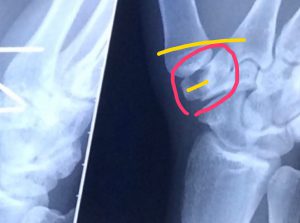

大阪桐蔭の優勝から一夜明け小僧は緊急入院に大会二回戦の試合中に右手大菱形骨を骨折し大会中は離脱したくないとテーピングでぐるぐる巻きに そして今手術中 イメージ写真折れた大菱形骨と開いた親指を戻す為に二箇所をビスで固定するみたいですなんかレアな骨折らしい